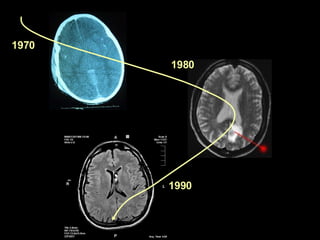

1970 1980 1990

2 questions : How does it look like ? CT Scan Structural MRI How does it work ? EEG + EP  PET-scan, fMRI

2 questions :How does it look like ? CT Scan Structural MRI How does it work ? EEG + EP PET-scan, fMRI